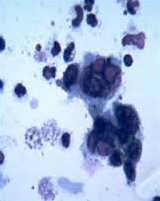

Tzanck smear = multinucleated giant cells

reacting T knight with 8's: Reactive cytotoxic CD8+ T cells (Downey, or atypical cells) lymphocytosis, seen on blood smear (stain on cloth)

tank: Tzanck smear = multinucleated giant cells